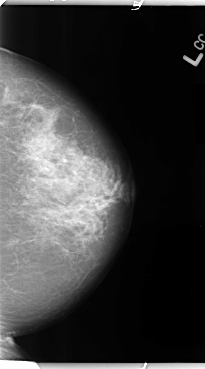

B_3116_1.LEFT_CC

LEFT_CC LINES 4792 PIXELS_PER_LINE 2664 BITS_PER_PIXEL 12 RESOLUTION 50 NON_OVERLAY